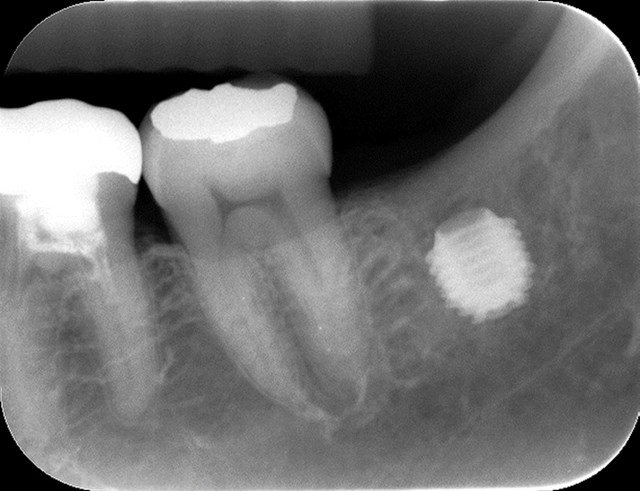

ここの付属病院で働いていらっしゃる平山先生に相談したら、「ドクター・シャディにしてもらおう。」と言われました。2014年11月にボストンに来た際、研修の空き時間に、シャディ先生にここで、バイコンのインプラントを入れていただきました。入れた時のX線写真がこれです。